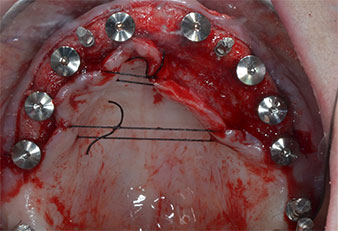

In pazienti edentuli, protesi fisse su impianti migliorano la masticazione e la qualità della vita. A causa del riassorbimento e dell'estesa pneumatizzazione dei seni, una paziente presentava solo una minima altezza dell'osso mascellare posteriore. Le sedi dell'impianto sono state preparate con un dispositivo piezoelettrico e un nuovo set di strumenti dedicati. Sono stati posizionati due impianti da 10 mm e sei da 4 mm per ancorare una protesi dentaria CAD/CAM fissa supportata da barra.

A causa dell'osso relativamente duro (D2) in quest'area, le sedi dell'impianto di 10 mm nelle posizioni 11 e 21 sono state finalizzate con un trapano rotante da 4 mm di diametro, in combinazione con un contrangolo chirurgico W&H WS-75 L, il motore per impianto W&H Implantmed e il modulo opzionale Osstell ISQ di W&H. Al contrario, a causa dell'osso morbido, le sedi posteriori sono state preparate a un diametro finale di 3 mm utilizzando lo strumento Piezomed I3P. Gli impianti sono stati infine posti per via transgengivale sull'osteointegrato per tre mesi (Figg. 6-10). La protesi dentaria esistente è stata mantenuta su quattro impianti provvisori (Fig. 8).